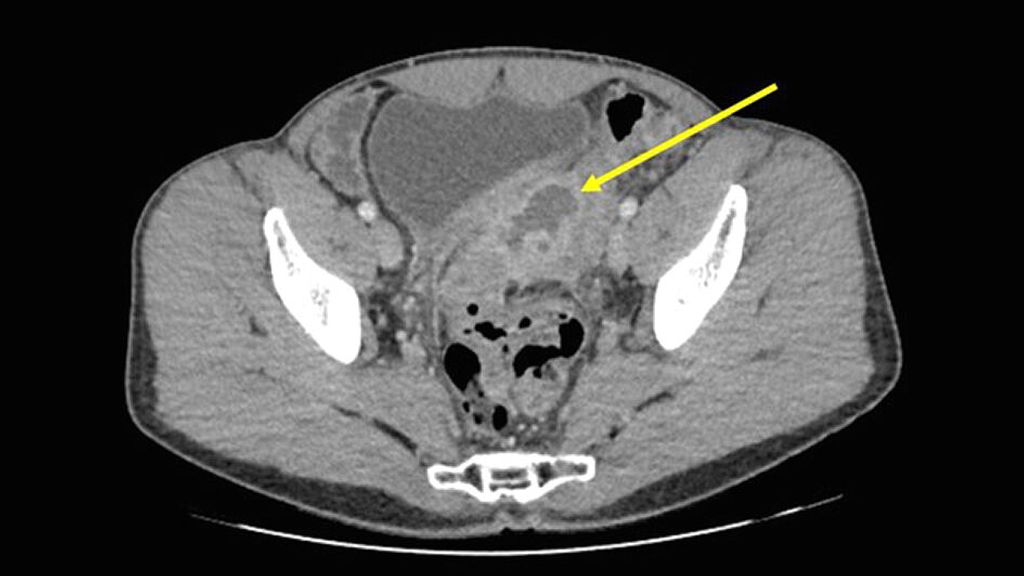

Kurz gesagt wird eine Divertikulitisepisode als «unkompliziert» definiert, wenn sie im Stadium HincheyIa ist, und als «kompliziert», wenn sie im Stadium >Hinchey Ia ist (Abb.1); auf Letzteres trifft etwa jede fünfte Episode zu.11 Das isolierte Vorhandensein von freier Luft in Abwesenheit von Abszessen und freier Flüssigkeit wird in der modifizierten Hinchey-Klassifikation nicht berücksichtigt. Obwohl wir dokumentiert haben, dass Patienten mit isolierter freier Luft ein stärkeres Entzündungssyndrom bei der Aufnahme haben als Patienten ohne freie Luft,12 sollte das Vorhandensein von isolierter freier Luft nicht dazu führen, dass diese Patienten überklassifiziert werden und die Therapiestrategie geändert wird.13 Eine Notoperation ist tatsächlich nur bei 6% dieser Patienten angezeigt14 – ein ähnlicher Anteil wie bei Patienten ohne freie Luft.12

Abb. 1: Komplizierte Divertikulitis im Stadium Hinchey Ib. Der gelbe Pfeil zeigt auf den parasigmoidalen Abszess, der die Blase verdrängt